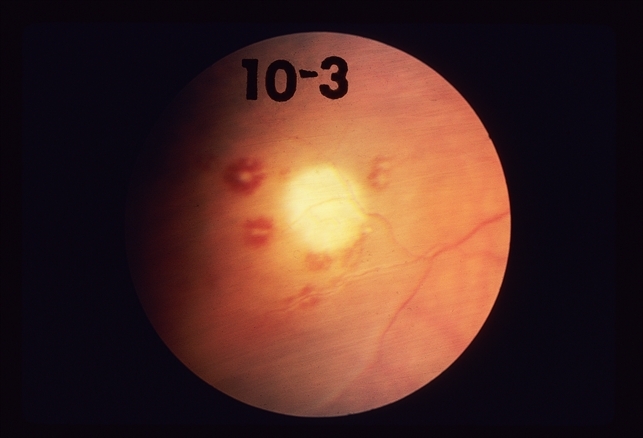

What are risk factors for developing subacute bacterial endocarditis? Infective endocarditis (ie) is defined as an infection of the endocardial surface of the heart, which may include one or more heart valves, the mural endocardium, or a septal defect. Subacute bacterial endocarditis bioinformatics tool. It can be confused with essential mixed cryoglobulinemia.cite. Subacute bacterial endocarditis (sbe), although aggressive, usually develops insidiously and progresses slowly (ie, over weeks to months). What you need to know. Subacute bacterial endocarditis (also called endocarditis lenta) is a type of endocarditis (more specifically, infective endocarditis). Classic peripheral signs of subacute bacterial endocarditis. Subacute bacterial endocarditis (sbe) is now an uncommon cause of fuo as rapid diagnostic capabilities have improved (echocardiology and blood culture methods). Bacterial endocarditis, infective endocarditis, infectious endocarditis, subacute bacterial endocarditis, acute endocarditis, osler node, osler's node, janeway lesion. After treatment, subacute bacterial endocarditis rarely leads to severe cardiac damage; Read more about symptoms, diagnosis, treatment subacute bacterial endocarditis (sbe) is the microbial infection of the endocardium with an indolent nature. Among the signs of subacute bacterial endocarditis are: